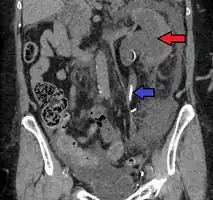

CT scan of bilateral hydronephrosis due to a bladder cancer -

Left sided hydronephrosis in a person with an atrophic right kidney. Stent is also present (image below). -

Left sided hydronephrosis, coronal view. Stent is also present.